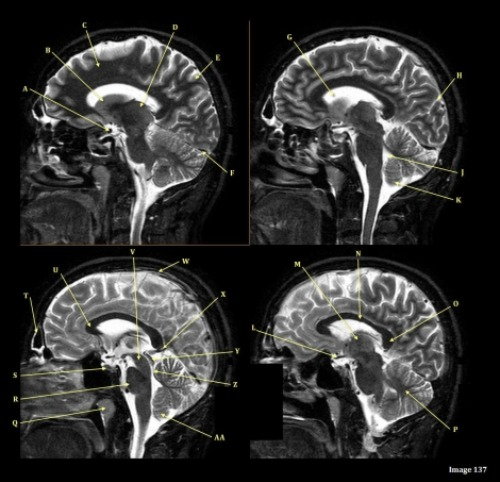

Image 8 is an example of a ____ weighted sequence acquired in the ____ scan plane.

A. T1; Axial

B. T1; Sagittal

C. T2; Axial

D. T2; Sagittal

Letter A in Image 8 is pointing to:

A. Tentorium

B. Corpus callosum

C. Hypothalamus

D. Fourth ventricle

E. Lateral Ventricle

Letter D in Image 8 is pointing to:

B. Cerebellum

C. Thalamus

E. Medulla oblongata

Letter B in Image 8 is pointing to:

Letter E in Image 8 is pointing to:

Letter F in Image 8 is pointing to:

Letter R in Image 137 is pointing to:

A. Pons

B. Cerebral peduncle

D. Caudate nucleus

E. Cerebellum

F. Basal vein

Letter N in Image 137 is pointing to:

C. Genu of corpus callosum

D. Body of corpus callosum

E. Splenium of corpus callosum

Letter J in Image 137 is pointing to:

A. Aqueduct of Sylvius

B. Third ventricle

C. Sulcus

E. Superior sagittal sinus

F. Lateral ventricle

Letter H in Image 137 is pointing to:

A. Grey matter

B. White matter

Letter O in Image 137 is pointing to:

Letter M in Image 137 is pointing to:

Letter X in Image 137 is pointing to:

A. Anterior frontal vein

D. Vein of galen

Letter B in Image 137 is pointing to:

Letter S in Image 137 is pointing to:

A. Optic chiasm

B. Pituitary gland

C. Inferior colliculus of midbrain

D. Internal carotid artery

E. Vein of galen

F. Straight sinus